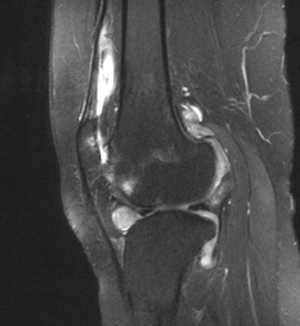

Image IQ: 11-year old Female with Bilateral Knee Swelling

An 11-year-old female presents with persistent chronic swelling of the right greater than left knees and stiffness limiting mobility.